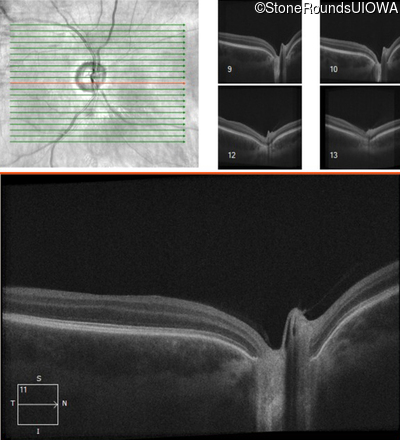

Age at visit: 17 years

This 17 year old male had normal vision until about 6 months earlier when he began to lose central vision. The left eye may have been affected prior to the right eye.

Leber Hereditary Optic Neuropathy MT-ND4 11778 A>G   MT